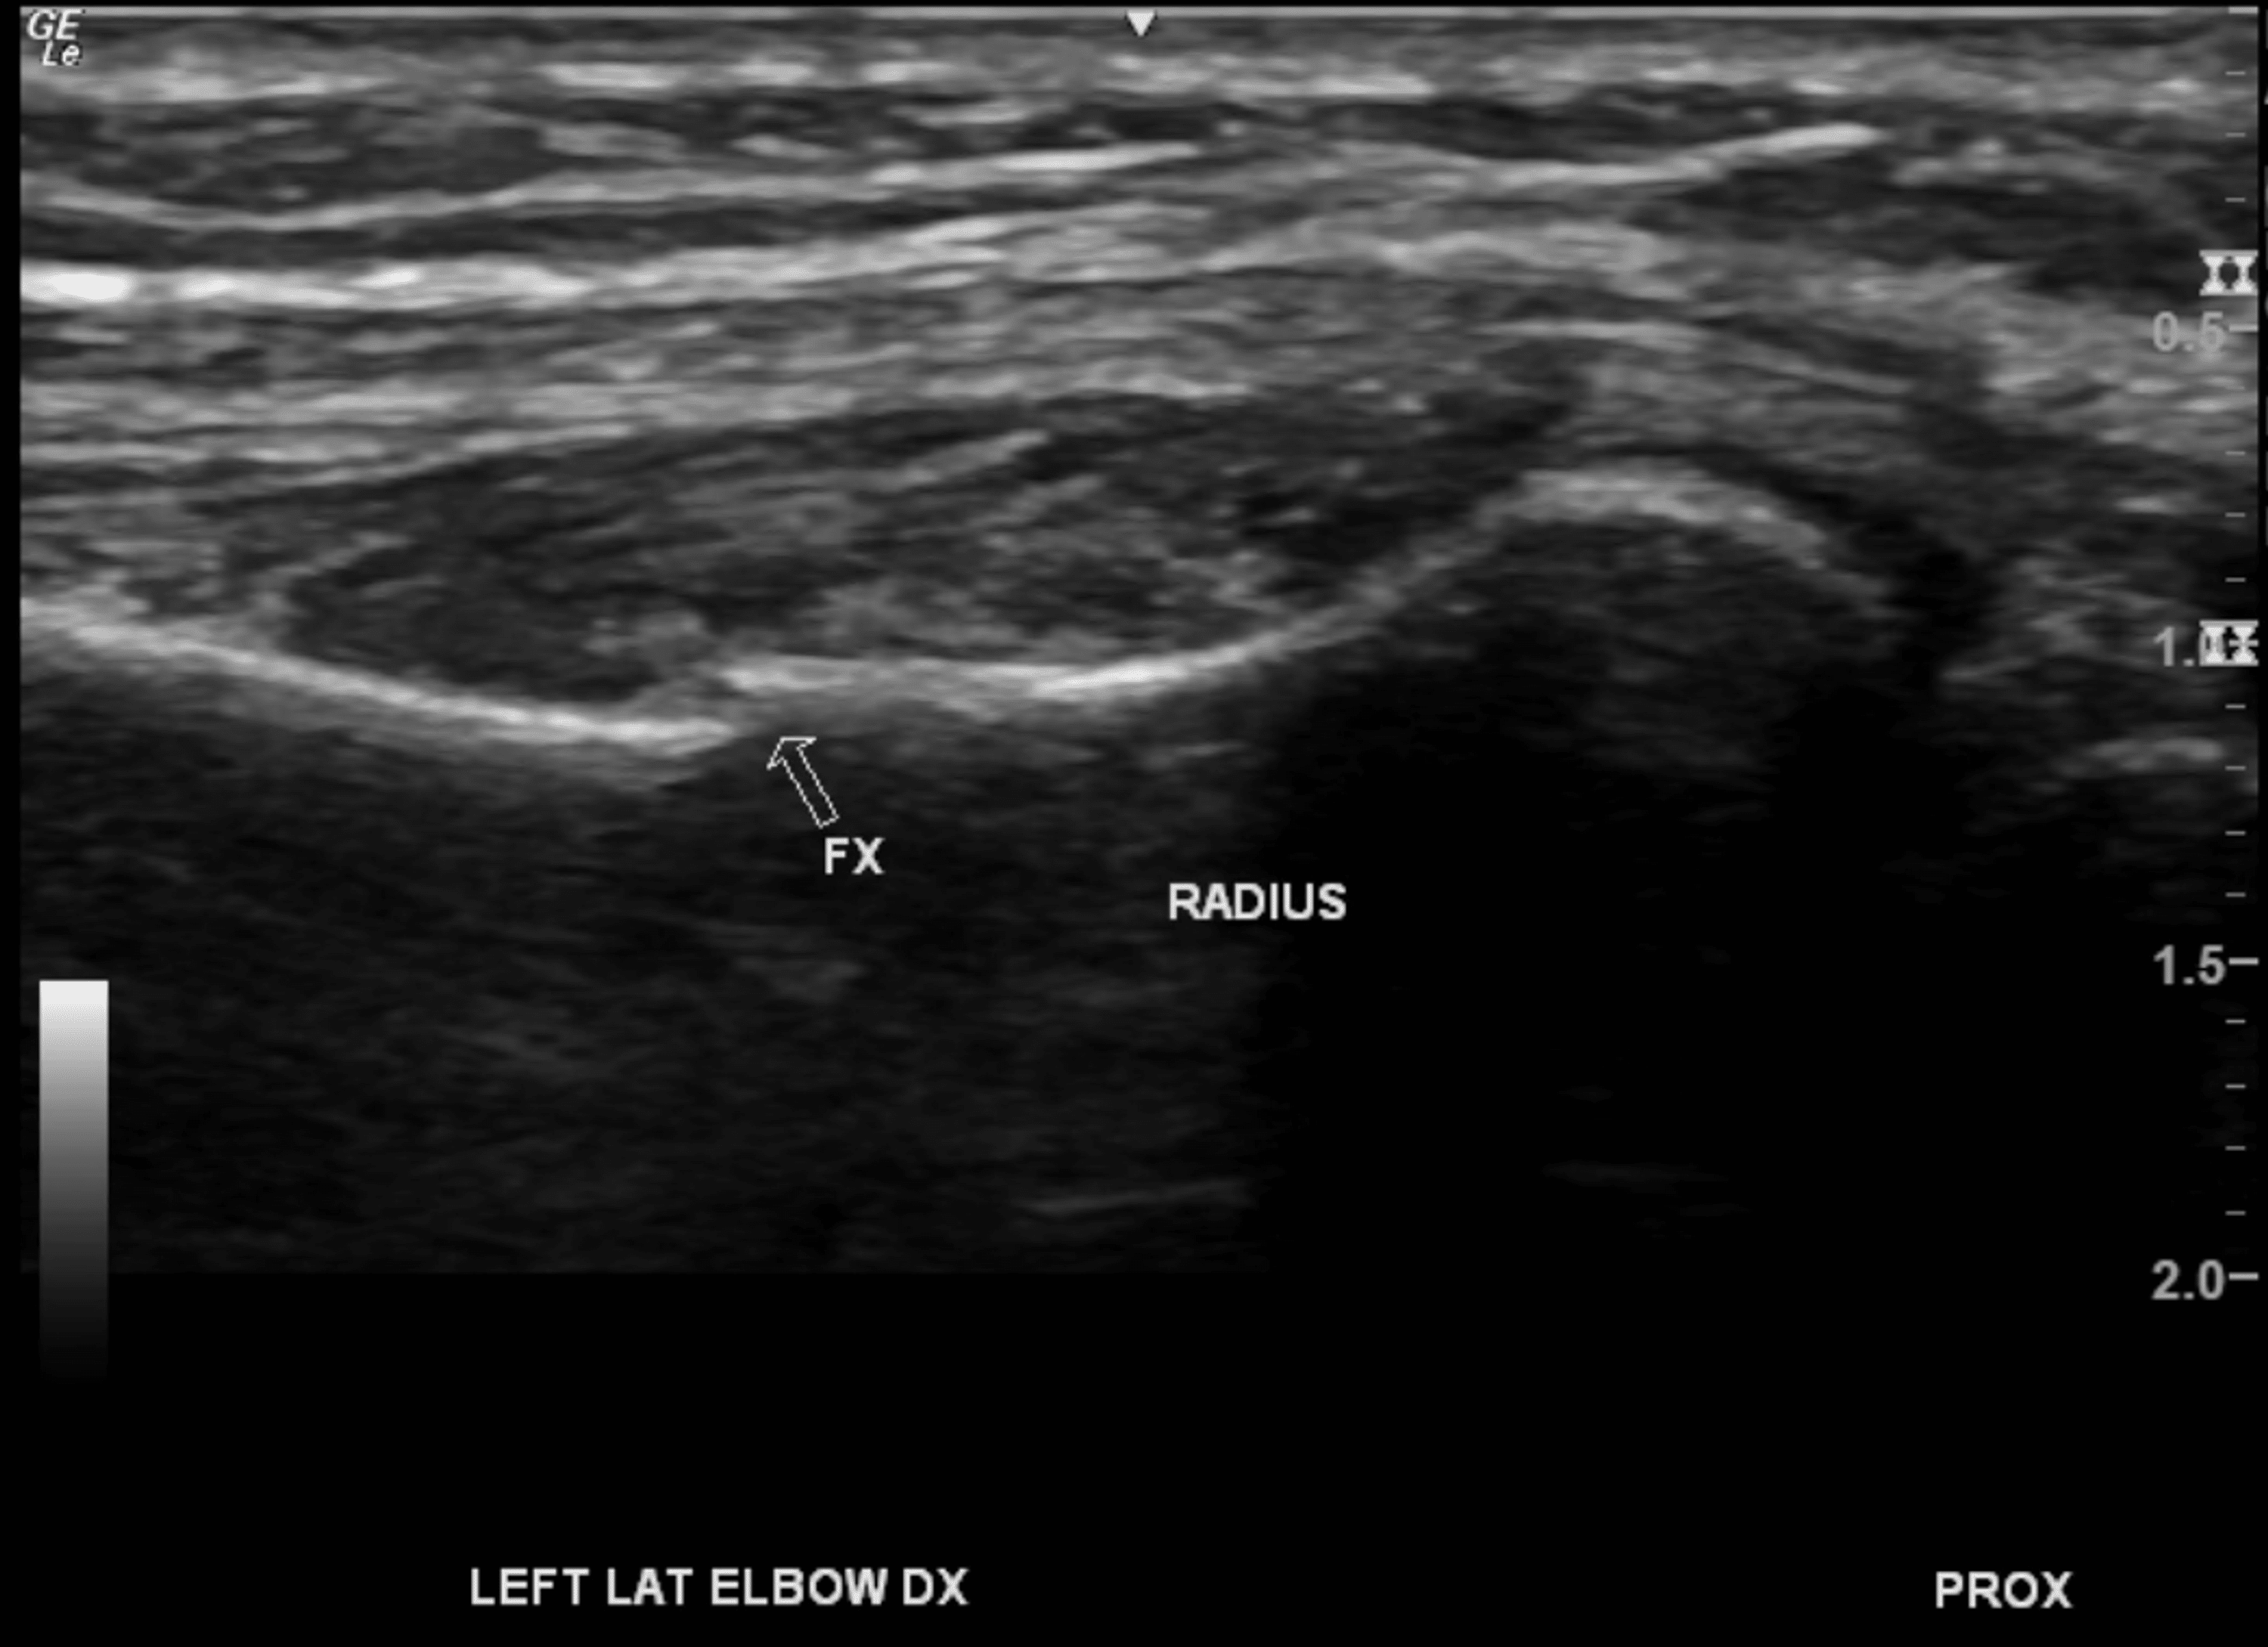

Utility of Computed Tomography and Ultrasound in Elbow Fracture Ultrasound And Fractures objective to determine the efficacy of low intensity pulsed ultrasound (lipus) for healing of fracture or osteotomy. four trials tested the effects of ultrasound on healing of 203 upper limb fractures and the other trials, on 130 lower. in this review, we summarized the role of ultrasound imaging in the management of bone fractures and. we. Ultrasound And Fractures.